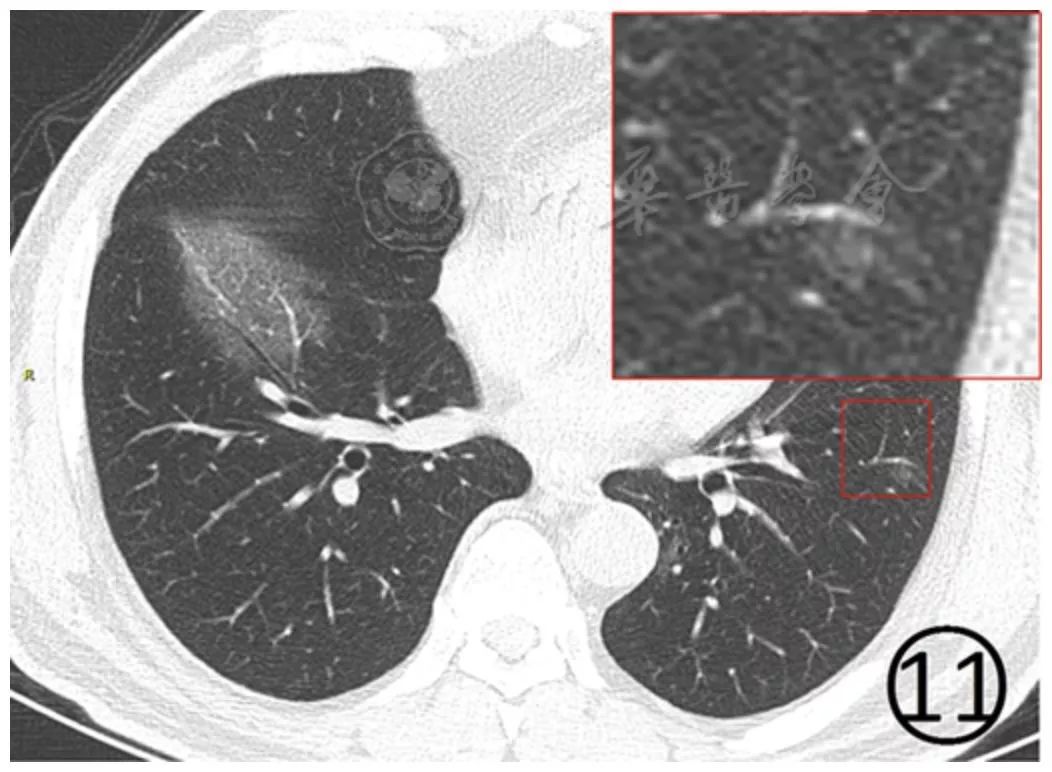

磨玻璃阴影内的细支气管管壁有增厚(图11),可见细支气管的充气支气管征(图11),血管影增粗,边缘欠光整,邻近的叶间胸膜有轻度增厚(图12)。

图11 男,51岁。CT平扫肺窗显示肺内大片和斑片状磨玻璃阴影,其内微血管增多,细支气管有支气管充气征,细支气管壁增厚,左下肺小血管周围有淡薄的磨玻璃阴影(方框)